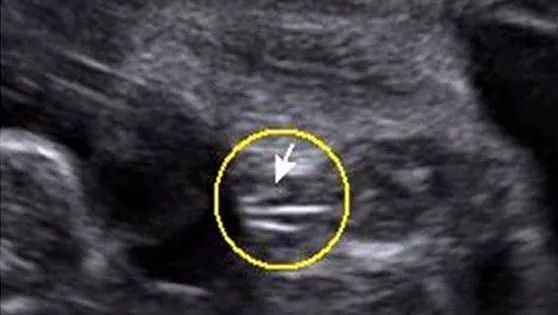

男宝宝四维彩超图

“凸出的东西” 是他的标记: 你们看到圆圆的是蛋蛋,如果看到圆圆的加小肠的就是全部JJ